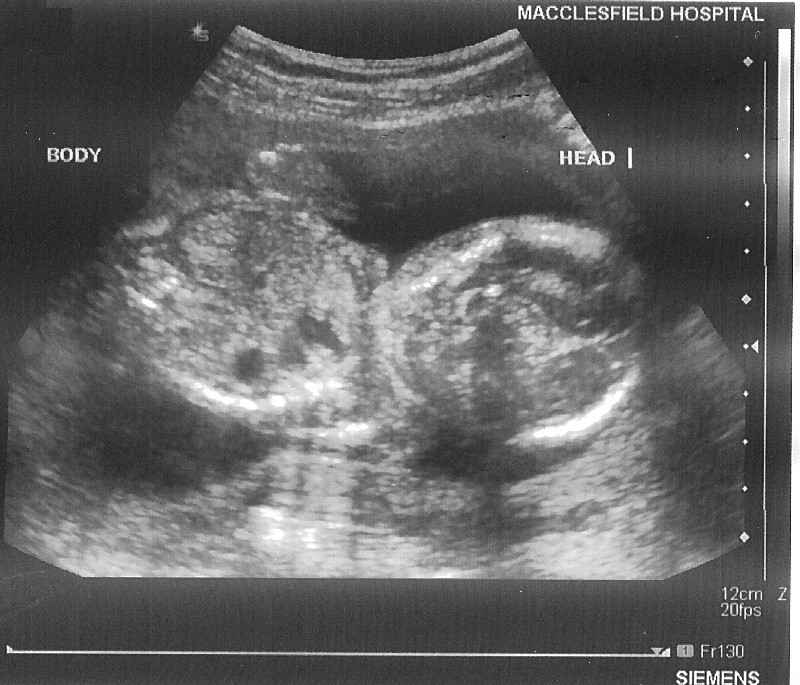

20 Week Hospital Scan on 14 March 2006